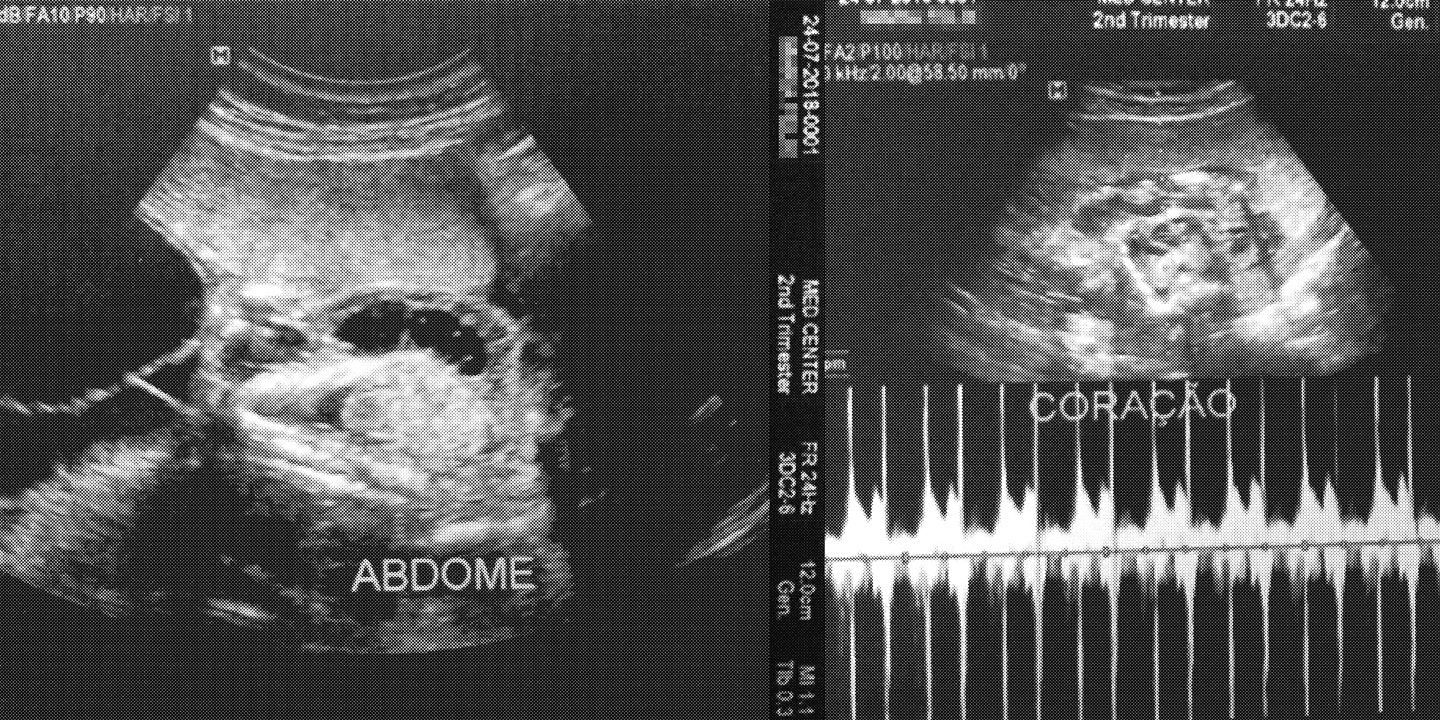

Ultrassom que constatou a má-formação no filho de Maria Félix. Ele morreu ainda no útero, com 25 semanas, por causa de má-formação no abdômen e no coração. Imagem: João Brizzi/The Intercept Brasil

17 Set 2018 – O filho de Maria Félix, de 21 anos, resistiu pouco mais de seis meses de gestação. Morreu ainda no ventre, com apenas 322 gramas. A causa do aborto, que aconteceu com 25 semanas de gravidez, foi má formação: o bebê tinha o intestino para fora do abdômen e também problemas no coração. Não é incomum que as mães da região percam seus filhos precocemente. O bebê de Maria, ao que tudo indica, foi mais uma vítima precoce do agrotóxico glifosato, usado em grandes plantações de soja e de milho em Uruçuí, a 459 km de Teresina, no Piauí.

Conheci a história de Maria Félix Costa Guimarães na maternidade do hospital regional Tibério Nunes, na cidade de Floriano. É para lá que as mulheres de Uruçuí são encaminhadas quando têm problemas na gravidez. Nos primeiros exames, feitos em julho, já havia sido identificada a má-formação no feto. Em setembro, no leito do hospital, encontrei a jovem, que lia a Bíblia e se recusava a comer. Carregava um olhar entristecido, meio envergonhado. Ela tinha sofrido o aborto no dia anterior e aguardava o médico para fazer uma ultrassom e se certificar de que não seria necessária a curetagem (cirurgia para retirada de restos da placenta).

Na maternidade de Floriano, o coordenador do setor de obstetrícia Luiz Rosendo Alves da Silva já viu muitos casos de aborto e de má-formação. Ele acredita na culpa dos agrotóxicos. “É uma contaminação lenta, gradual e diária. A principal consequência é a atrofia de alguns órgãos, principalmente coração e pulmão”.